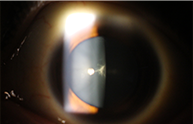

• 백내장 없는 눈

• 백내장 있는 눈

[백내장 질환]

• 20대 후낭하 백내장

• 원모양 핵 백내장

• 피질 백내장

• 심한 백내장으로 인해 실명 된 성숙 백내장